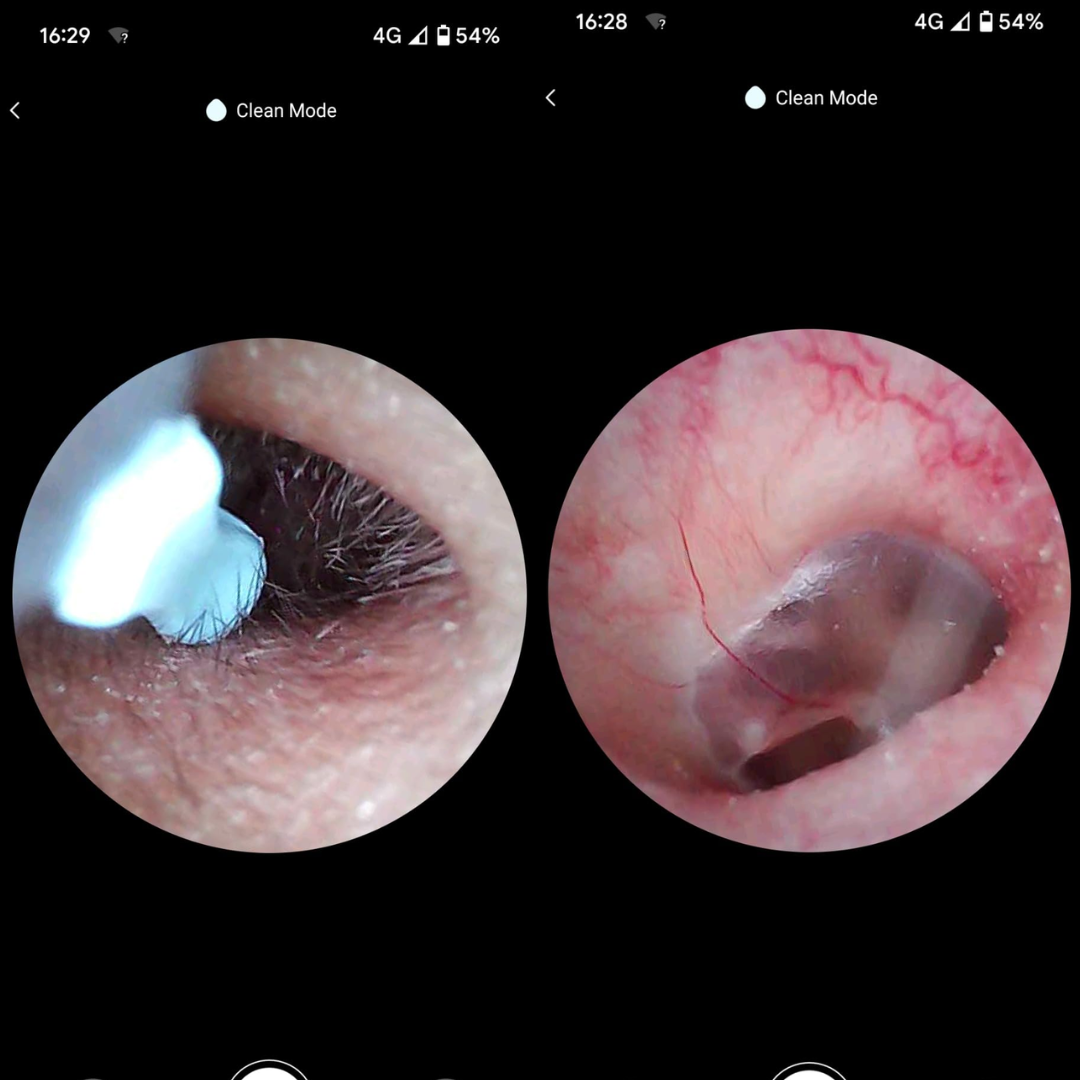

✅ Wyraźny obraz HD – dokładna widoczność wnętrza ucha dzięki kamerze 1080p

Koniec z ryzykiem urazów i infekcji — patyczki często powodują podrażnienia, infekcje i perforację błony bębenkowej. Pełna kontrola dzięki obrazowi HD 1080p — widzisz woskowinę i swobodnie ją usuwasz, zamiast ją wpychać.

Pełna kontrola dzięki obrazowi HD 1080p — widzisz woskowinę i swobodnie ją usuwasz, zamiast ją wpychać. Miękkie silikonowe końcówki zamiast patyczków — precyzyjnie usuwa woskowinę, bez ryzyka zarysowań i dyskomfortu